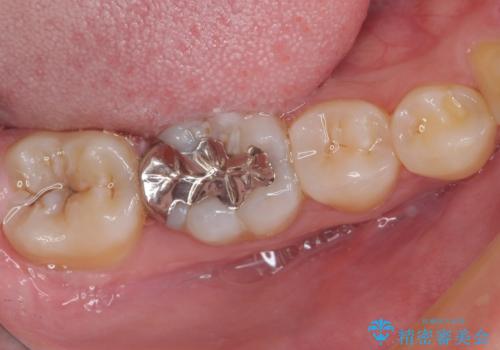

- 矯正治療後に目立つ銀歯を白くしたいとのことで来院された患者様です。

右下の銀の詰め物は、外してむし歯を除去した後、セラミックインレーにて修復することとしました。